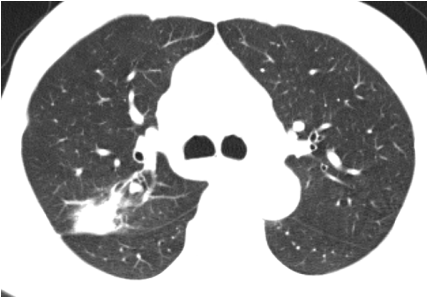

经过精心治疗,王某的症状完全消失。一个月后复查胸部 CT,结果显示较前明显吸收,这标志着王某的病情得到了有效控制,向着康复迈出了坚实的一步。信丰县中医院肺病科专家团队以卓越的医疗水平和高度的责任心,再次为患者带来了健康和希望,也赢得了广大患者的信任和赞誉。

治疗后CT影像▲